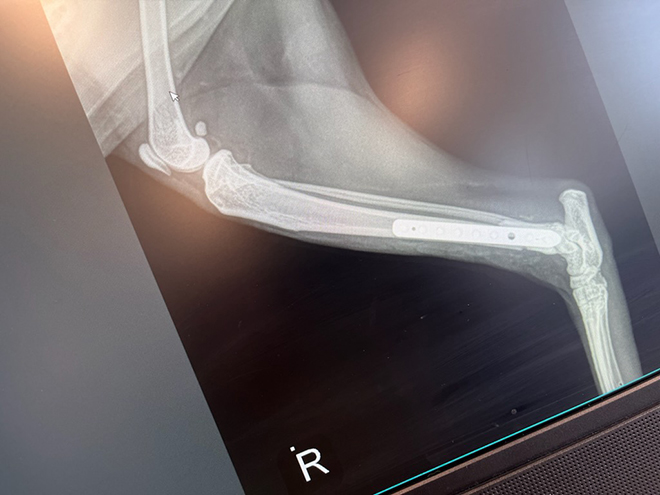

Sphinx the black cat disappeared. I was pretty much done searching and calling and crying when who should drag herself up on the deck but Sphinx. We are still not sure what happened to her but she was terribly stressed and a back leg was obviously broken.

Luckily we have a son and daughter in law who are veterinarians. So they got a call at 5:30 Friday afternoon to please stay at the clinic – Friday is usually son Todd’s day off but he had had a busy day, was still at work late and got the bad news that his mother was bringing her cat up in 2.5 hours.

A surgery and 4 weeks later we got a call that we could come and pick HIM up.